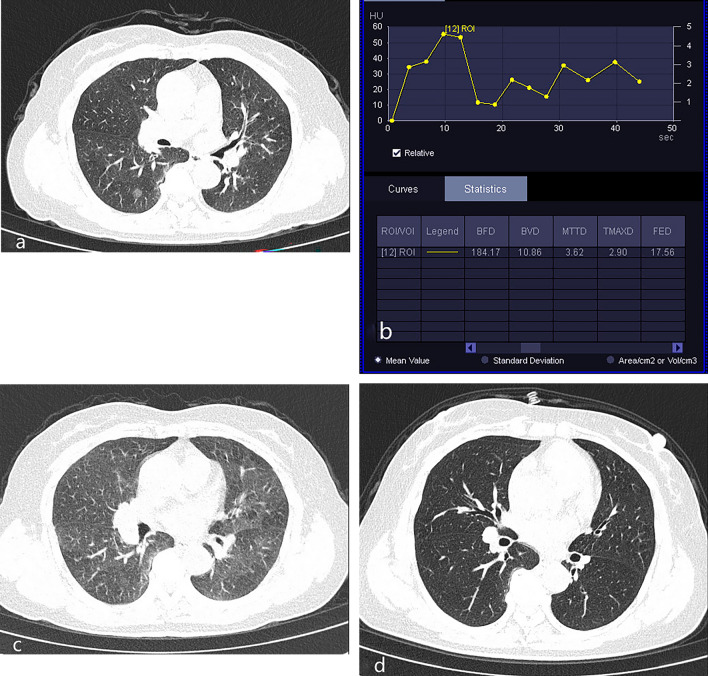

Figure 4.

Invasive adenocarcinoma. A 56-year-old man underwent physical examination, which revealed pulmonary nodules. (a) Plain CT showed part-solid GGO nodules in the upper lobe of the right lung. (b) Based on the TDC of CT perfusion of the part-solid nodule, the curve shows a rapidly increasing pattern followed by a slowly decreasing pattern.